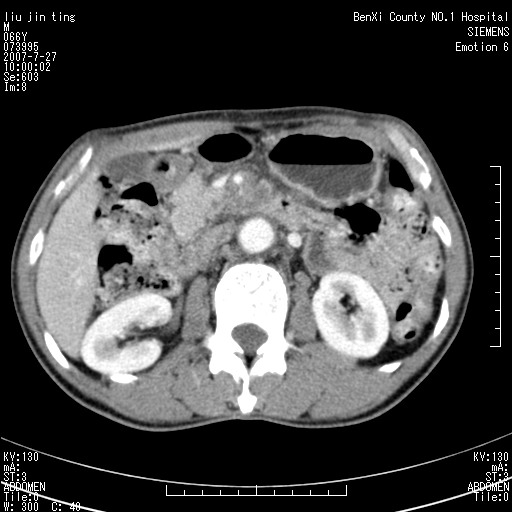

腹痛,背痛,无恶心呕吐,不黄,彩超示胰腺钩癌,ct扫描病灶平扫30-40hu,增强后动脉期40--60hu,静脉期50-68hu,真的是钩突上的么?您要试一试么?

动脉期

沿着肠系膜上动脉呈匍匐性生长的软组织肿块,形态不规则,包绕肠系膜上动脉,呈明显强化,考虑来源于肠系膜的恶性肿瘤

肠系膜根部肿块,累及肠系膜上动脉,考虑肿大淋巴结累及肠系膜上动脉.

沿着肠系膜上动脉呈匍匐性生长的软组织肿块,形态不规则,包绕肠系膜上动脉,呈轻-中度强化,考虑来源于肠系膜的恶性肿瘤。

钩突是正常的,只见腹膜后淋巴结的肿大,考虑淋巴瘤或转移可能。

支持!恶性纤维组织细胞瘤可能,与淋巴瘤及淋巴结转移鉴别(腹主动脉周围清晰,其他部位亦未见明显肿大淋巴结)。